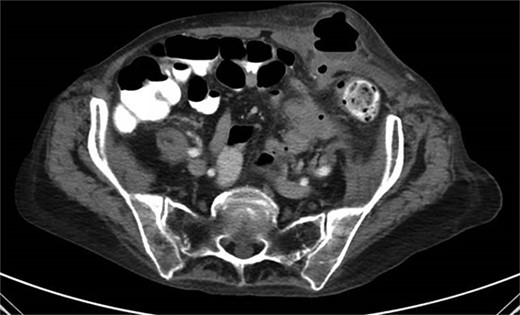

A 65-year-old female with a history of hyperlipidemia, hypertension, hip replacement, lumbar spinal fusion, chronic pain management, and prior laparotomy for endometriosis presented with a 3-day history of nausea, vomiting, and abdominal pain. She had no prior history of diverticulosis or colonoscopy. On examination, she was afebrile and hemodynamically stable. Physical examination revealed left lower quadrant tenderness, swelling, erythema, and fluctuance, suggesting an abdominal wall abscess (Figs 1 and 2). Laboratory tests showed leukocytosis with a count of 24.6 and a positive urinalysis with 2+ leukocytes. A CT scan of the abdomen and pelvis revealed a 3.8 × 3.6 cm air and fluid pocket in the low left anterior abdominal wall, indicative of an abscess likely at the site of a previous drain (Fig. 3). Additionally, there was a 2.8 × 1.8 cm irregular air pocket in the left pelvis, where an abscess had been identified in prior imaging.

CT from readmission with anterior abdominal wall abscess and left pelvic abscess.